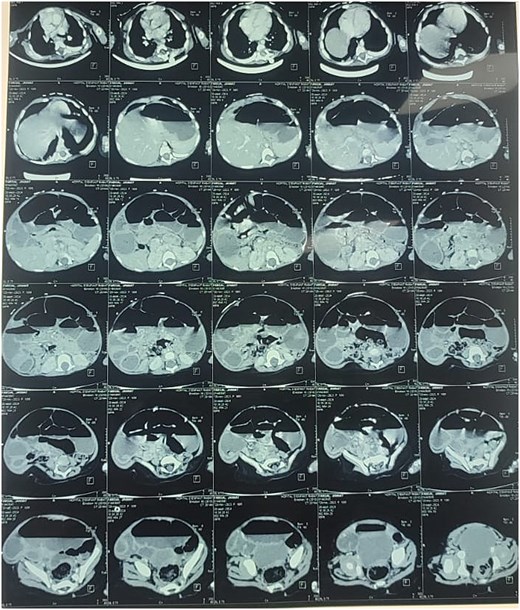

Reviewing the medical record of the patient, she underwent variable blood tests that were negative mostly except for ionogram disturbances due to malnutrition and dehydration. An abdominal X-ray was performed at each episode of hospitalization, that revealed intestinal-type hydroaeric levels and gastric stasis (Fig. 1) then a digestive fibroscopy with multiple biopsis as well as eosogastroduodenal transit were run out suggesting gastritis. A barium index (Fig. 2) was also performed on his last hospitalization suggesting a small bowel obstruction which also appeared on the Enteroscan (Fig. 3).

Enteroscan image showing an intestinal distension downstream of an obstacle.